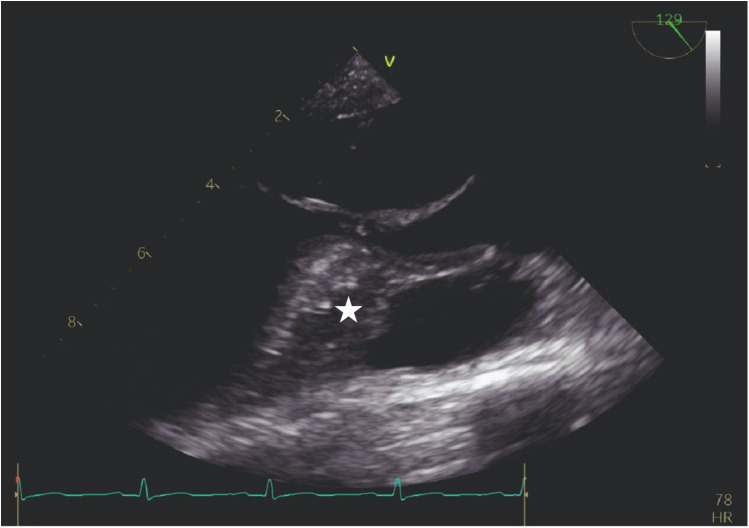

Methods: This study included 14 patients (8 females, 6 males), with symptomatic hypertrophic obstructive cardiomyopathy who underwent ASA between the years 2017 and 2025. Because of the unavailability and the high cost of contrast agents in our country, we used practical physiological agents, which comprised a cocktail fluid (agitated 5 mL of saline plus 0.5 mL blood of the patient). We injected ethanol (absolute alcohol 96%-99%) into the target perforatory artery using transesophageal echocardiography (TEE) in a step-by-step manner to observe a reduction in mitral regurgitation and QT prolongation at electrocardiographic monitorization (initially, 0.5 mL alcohol, then by increasing the dosage up to 3 mL).

Results: We clearly obtained a good myocardial opacification of the interventricular basal septum border with our cocktail contrast agent. Furthermore, we used TEE in the ASA procedure, unlike other researchers who reported on this procedure. No arrhythmias and allergic reactions were recorded during the administration of the contrast agent. The mean dose of alcohol administered during ASA was 2.1 ± 0.7 mL. The procedural rate of success was highest (100%). We assessed the effectiveness of the treatment in terms of a reduction of the peak left ventricular outflow tract gradient and the disappearance of severe mitral regurgitation with a significantly systolic anterior motion.